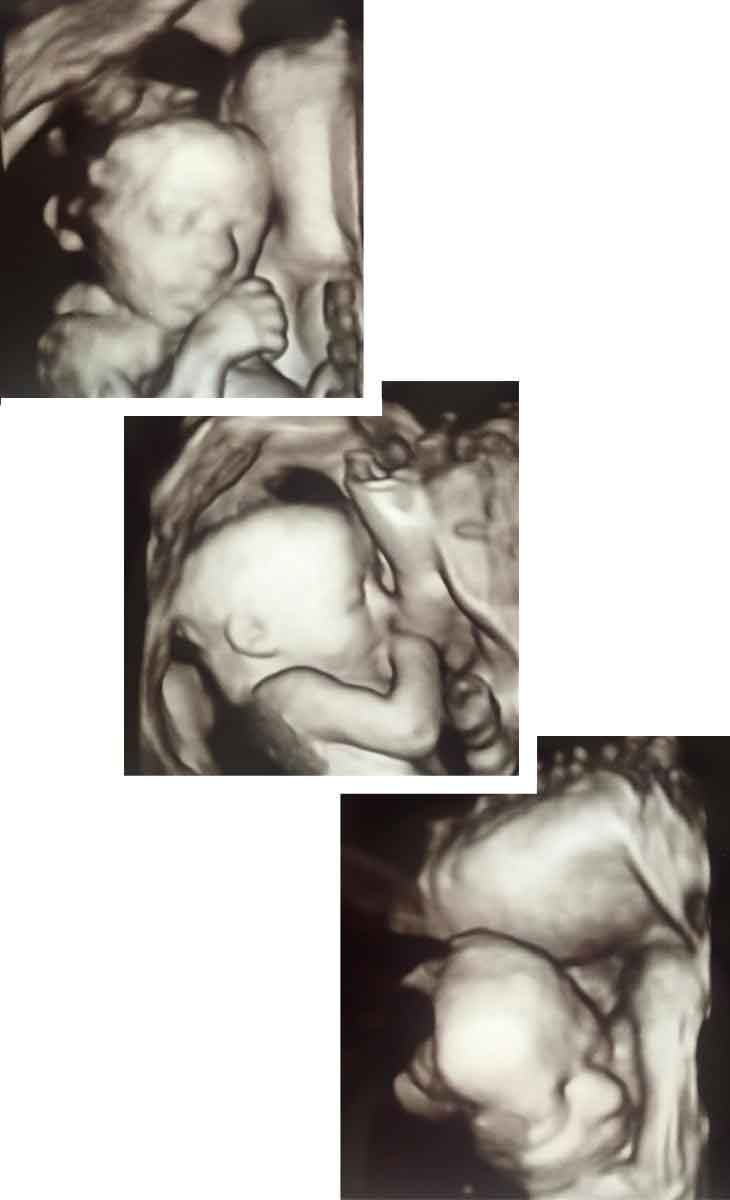

The photos are a selection of Luna from that final scan. You can also see Halle’s spine across the top of one - I love that one! Early Days Baby Scan in Wakefield was where we went, would definitely recommend.